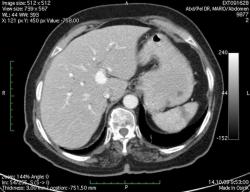

КТ брюшной полости. Женщина 73 года с жалобами на запоры.

Пациентка женщина 73 года. Предъявляет жалобы на запоры, спастические боли в брюшной полости.

ИзображениеЦиркулярное сужение в поперечной ободочной кишке. Ни это ли причина проблемм?

Новообразование в среднем отделе поперечной ободочной кишки с циркулярным сужением просвета и хронической механической толстокишечной непроходимостью. Признаков метастазирования в данной анатомической области не обнаружено. Пациент безусловно нуждается в хирургическом лечении.

Я не занимаюсь КТ, но сам характер сужения толстой кишки как-то вызывает сомнения, ракового ли он характера? Сужение то циркулярное, но больно уж ровненькое и нет признаков инфильтрации вокруг (хотя рак, конечно может иметь и такой вид). Ну, думаю dr.Mario со временем откроет карты и будет дана гистология.

Циркулярная стенозирующая опухоль (аденокарцнома) толстого кишечника; с типичной КТ презентацией и признаками обструкции. Пациентка была оперирована на второй день после КТ.